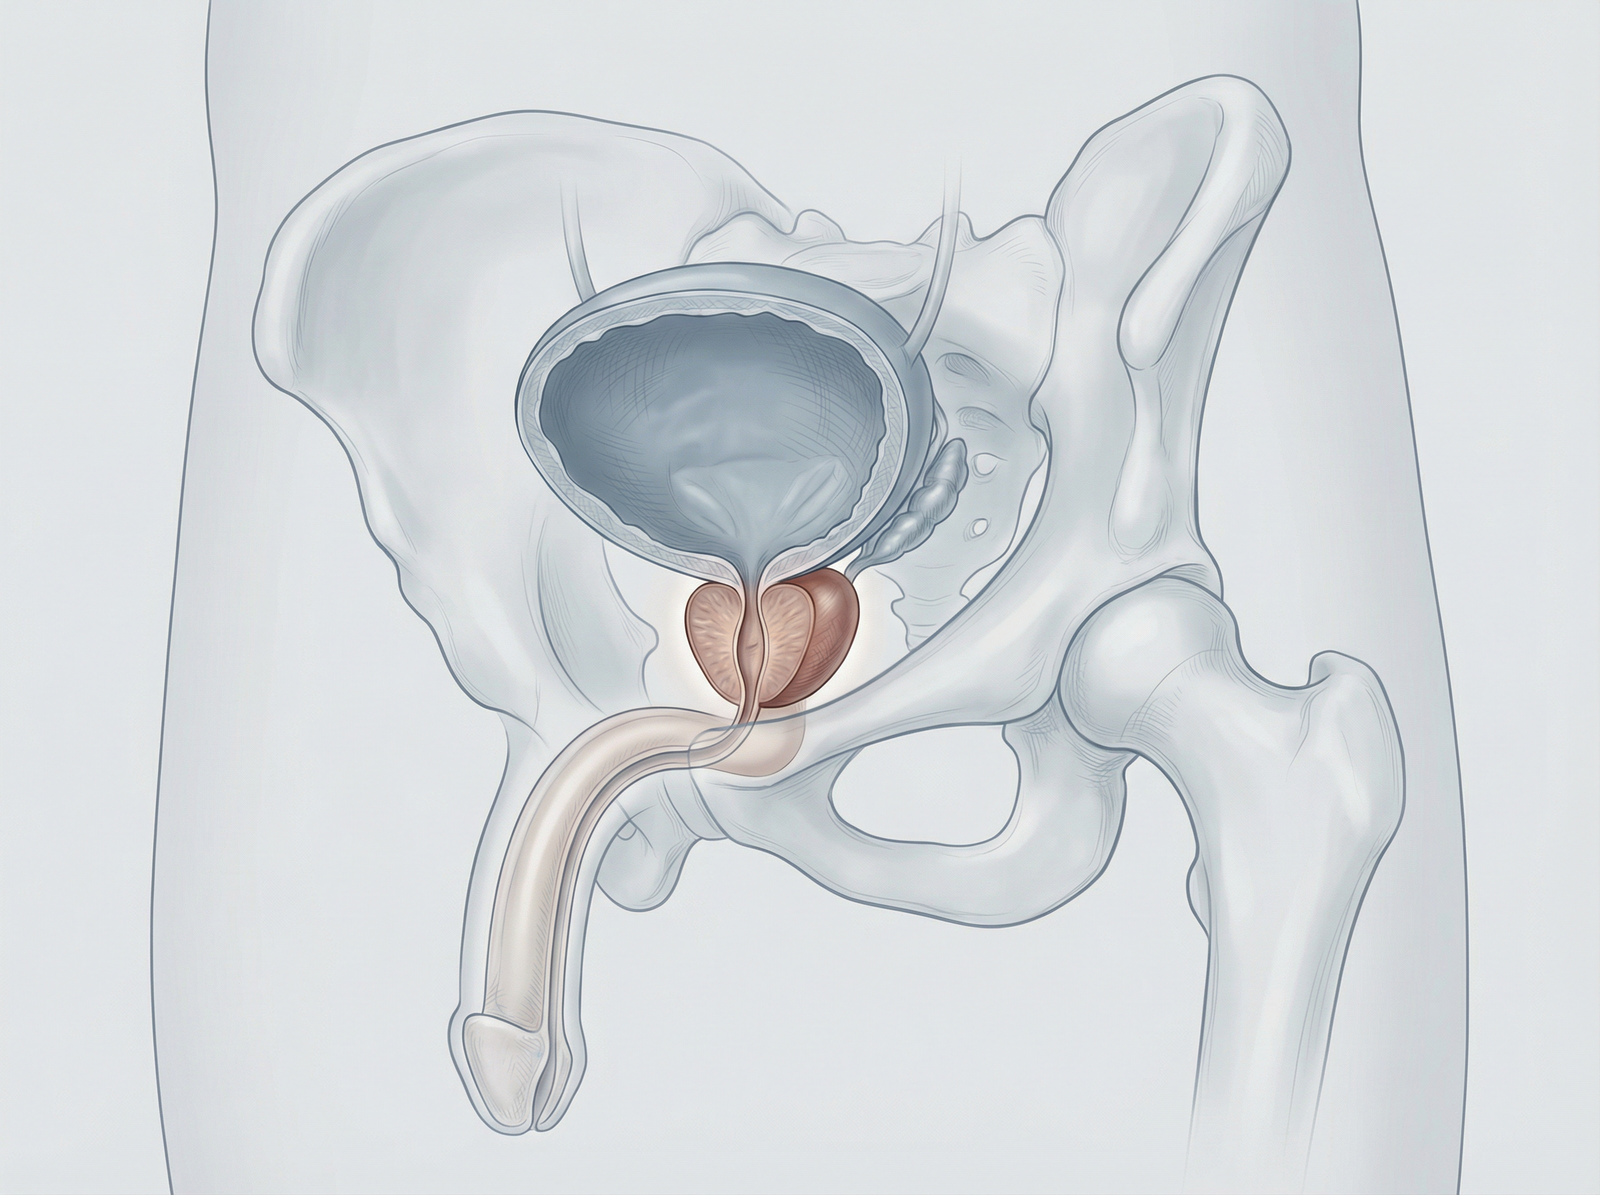

Enucleazione laser a fibra di tulio della prostata (ThuFLEP). Tecnica avanzata e mininvasiva per il trattamento dell’ipertrofia prostatica benigna, che consente la rimozione precisa del tessuto in eccesso con minimo sanguinamento. Recupero più rapido, maggiore sicurezza e miglioramento significativo dei sintomi urinari, per una migliore qualità della vita.

Hai problemi ad urinare a causa dell’ingrossamento della prostata? Presso la clinica Fabjan in Slovenia eseguiamo l’enucleazione laser della prostata con il laser a fibra di Thulium – ThuFLEP.